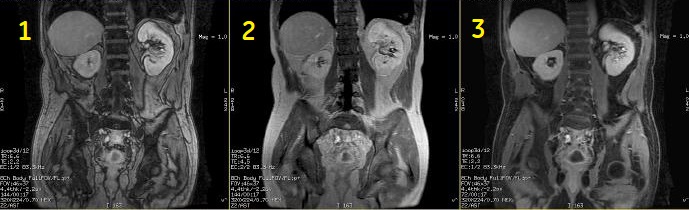

| Number | Description |

|---|---|

| 1 | out-of-phase |

| 2 | in-phase |

| 3 | water only |

Image Annotation

M3D/LAVA/flip angle: Water and Fat images are synthesized from collected in-phase and out-of-phase images; thus TE values for Water and Fat images are the average of IN-phase and Out-of-Phase TEs. In-phase and out-of-phase gets annotated according to the TE and TE2 values on screen.